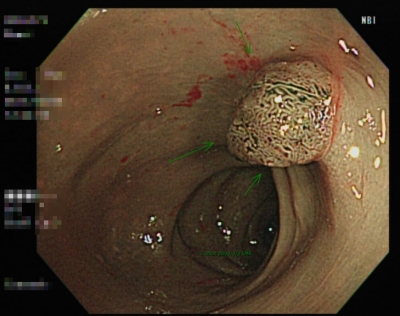

日前有30~39歲年齡層發生個案,分別為34歲莊小姐及38歲王先生兩位到北投健康管理醫院進行NBI無痛大腸內視鏡檢查,透過高端影像可清楚看見兩位體內已暗藏有高風險癌變的腺瘤,也在當次檢查中將息肉切除,免除了該息肉在日後發展成大腸癌的可能。

有大腸癌危險因子的年輕族群,千萬不可掉以輕心

日前有30~39歲年齡層發生個案,分別為34歲莊小姐及38歲王先生兩位到北投健康管理醫院進行NBI無痛大腸內視鏡檢查,透過高端影像可清楚看見兩位體內已暗藏有高風險癌變的腺瘤,也在當次檢查中將息肉切除,免除了該息肉在日後發展成大腸癌的可能。

【個案說明】

王先生,38歲,發現腺瘤型息肉(綠色箭頭處),大小約1.5 公分,病理化驗後有絨毛成分,大小與病理結果均符合世界衛生組織認定的有高風險癌變的進行性腺瘤。